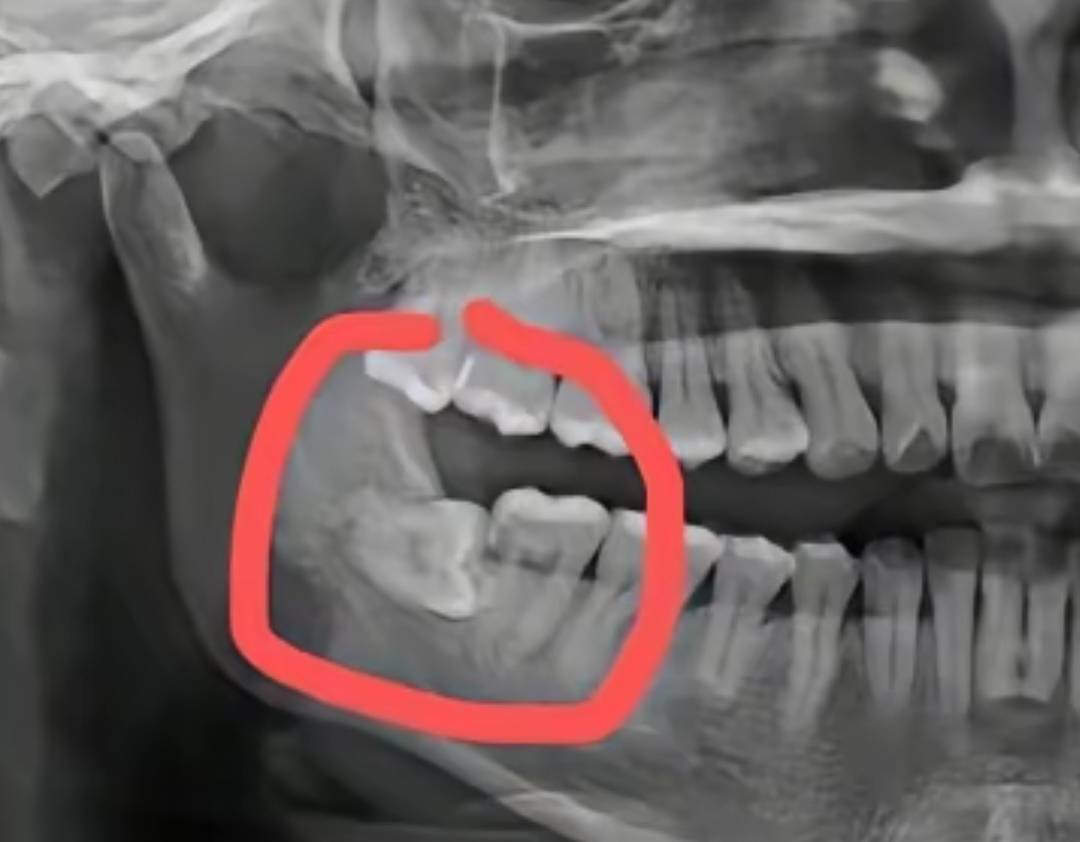

中午要去拔智齿了,有点害怕,像图片这种横着长的,不拔不行了,这两天疼的要死,而且有点烂了,发臭很严重,一张嘴一股那种腐烂的臭味铺面而来中午要去拔智齿了,有点害怕,像图片这种横着长的,不拔不行了,这两天疼的要死,而且64 / 作者:挂壁老哥饿了mm / 中午要去拔智齿了,有点害怕,像图片这种横着长的,不拔不行了,这两天疼的要死,而且7 / 作者:挂壁老哥饿了mm / 中午要去拔智齿了,有点害怕,像图片这种横着长的,不拔不行了,这两天疼的要死,而且10 / 作者:挂壁老哥饿了mm /